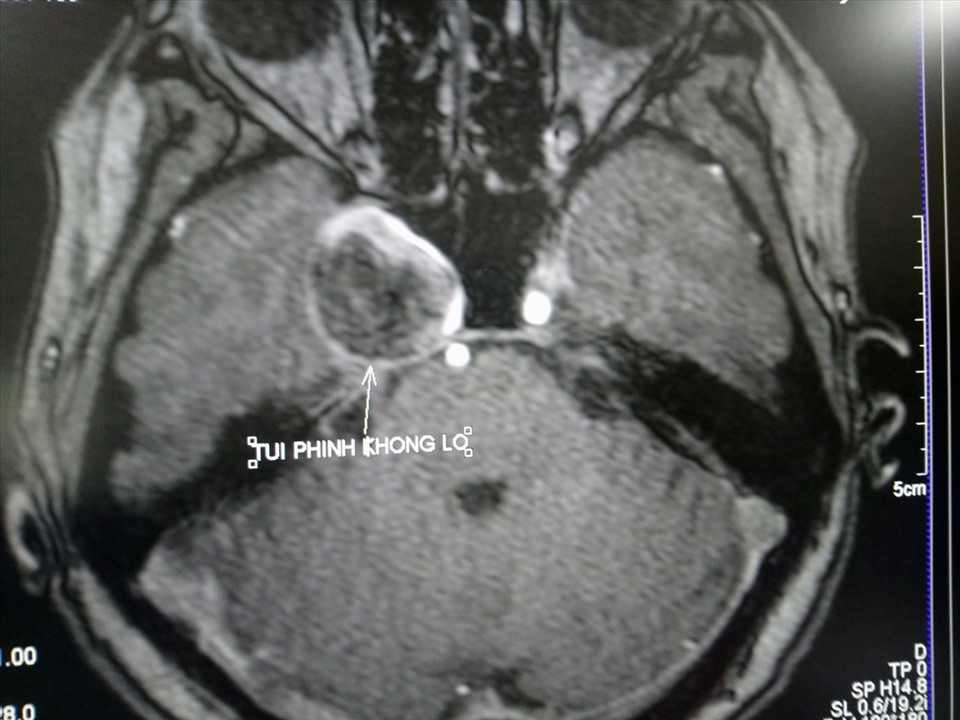

- Chụp cộng hưởng từ (MRI) với chuỗi xung MRA ( tái tạo mạch máu não 3D) cho phép xác định vị trí, kích thước của túi phình.

Hình ảnh phình động mạch cảnh trong phải khi chụp MRI sọ não với chuỗi xung MRA